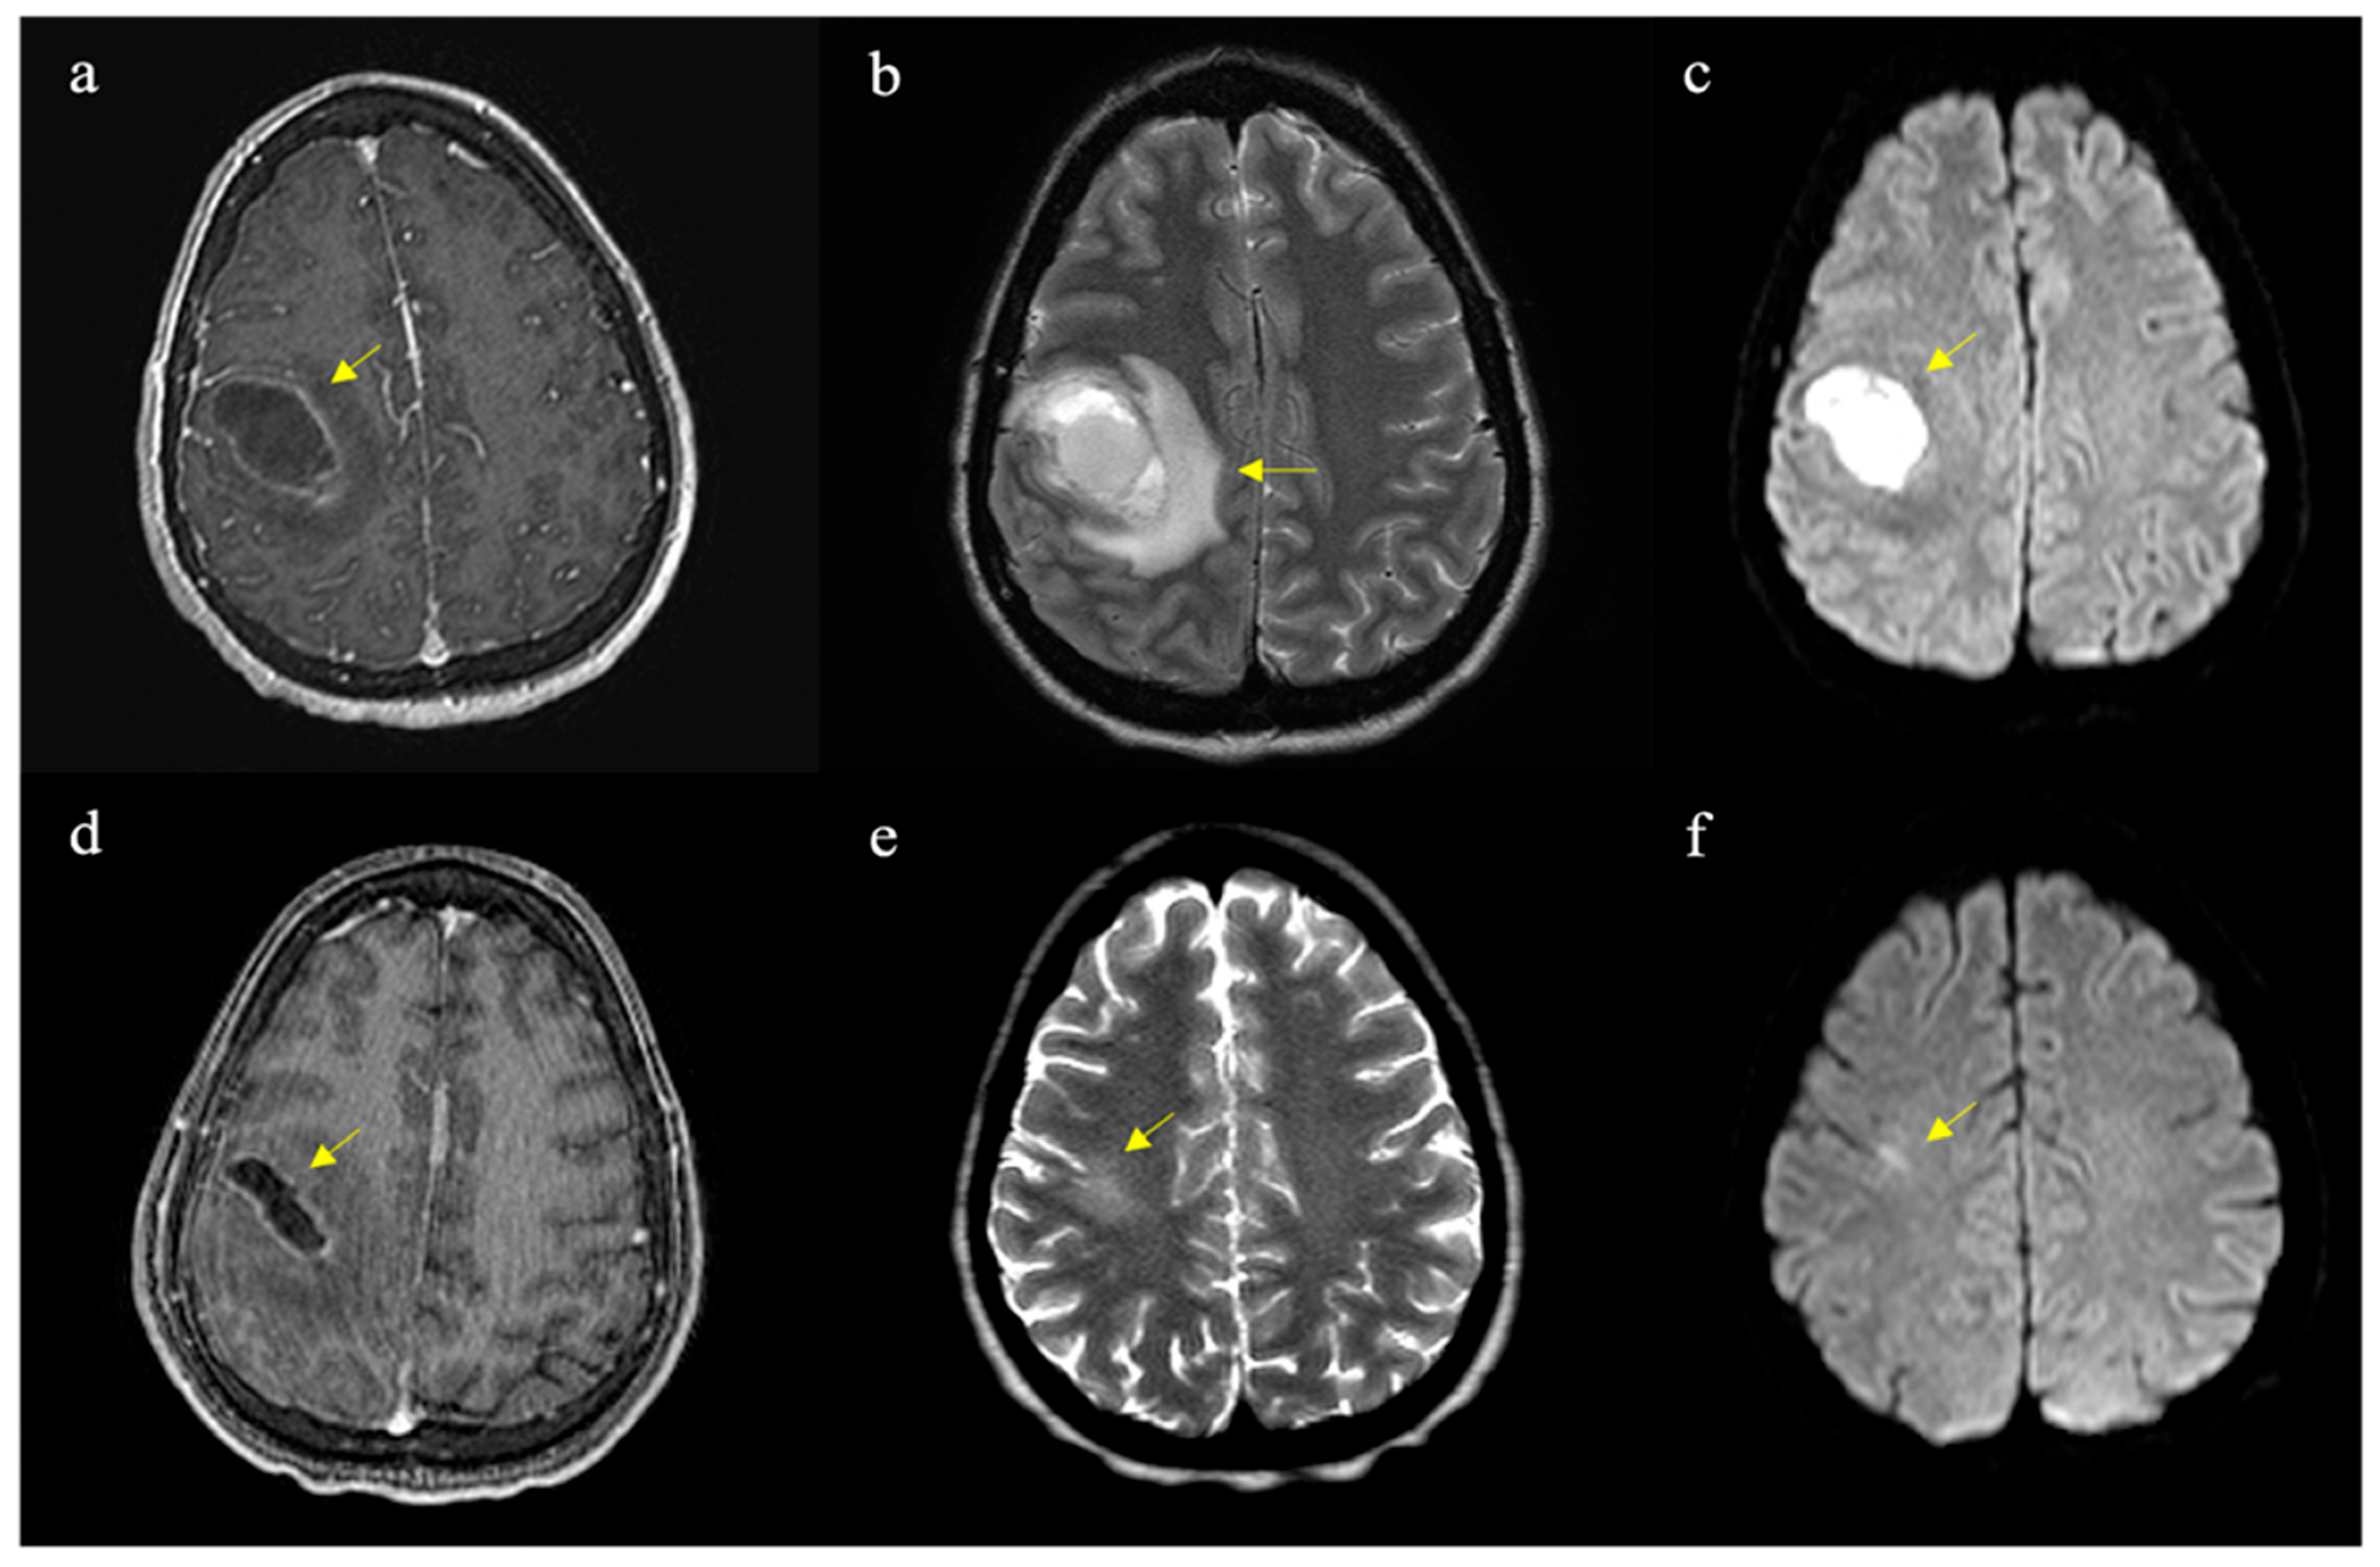

On physical examination, the patient appeared drowsy, with noted LUE weakness (strength Grade IV in shoulder abduction, elbow flexion/extension, and Grade III in wrist flexion/extension and hand grip). Laboratory results showed severe anemia (Hb 5.2, Hct 16%), leukocytosis (WBC 15,800), thrombocytosis (platelets 852,000), and elevated inflammatory markers (ESR 126 mm/h, ferritin > 1000, CRP 3). CT imaging revealed a 3.2 cm × 3.2 cm hypodense mass with surrounding vasogenic edema in the right frontoparietal region, causing a 3.5 mm leftward midline shift (Figure 1a). MRI findings were consistent with a solid-cystic heterogeneous lesion with ring enhancement and hyperintensity on DWI, suggestive of a brain abscess (Figure 1b). She was transfused with one unit of packed red blood cells and transferred to our hospital the next day. She underwent frameless stereotactic evacuation of the brain abscess, with 20 cc of purulent drainage sent for cultures. Empiric antibiotic therapy with vancomycin, cefepime, metronidazole, and dexamethasone was initiated postoperatively.

Figure 1. Axial MRI images pre- and post-operatively with different weightings. Typical abscess findings are indicated by arrows in each panel: (a) T1-weighted with contrast showing ring enhancement, (b) T2-weighted showing adjacent edema, (c) diffusion-weighted imaging (DWI) demonstrating marked hyperintensity, (d) 8-day post-operative T1-weighted image with contrast showing reduction in abscess volume compared to (a), and late (4-month) post-operative images showing slight residual hyperintensity in T2 (e) and no water restriction on the DWI (f) sequences.